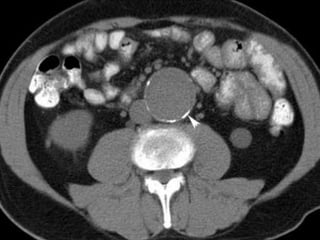

 Abdomen (cholecystitis, pancreatitis, aortic

aneurysm, peptic ulcer disease, nephrolithiasis,

pelvic inflammatory disease, diverticulitis)

48 year old woman severe LBP for six months despite swimming,

NSAID, PT, muscle relaxers, opiates, injections